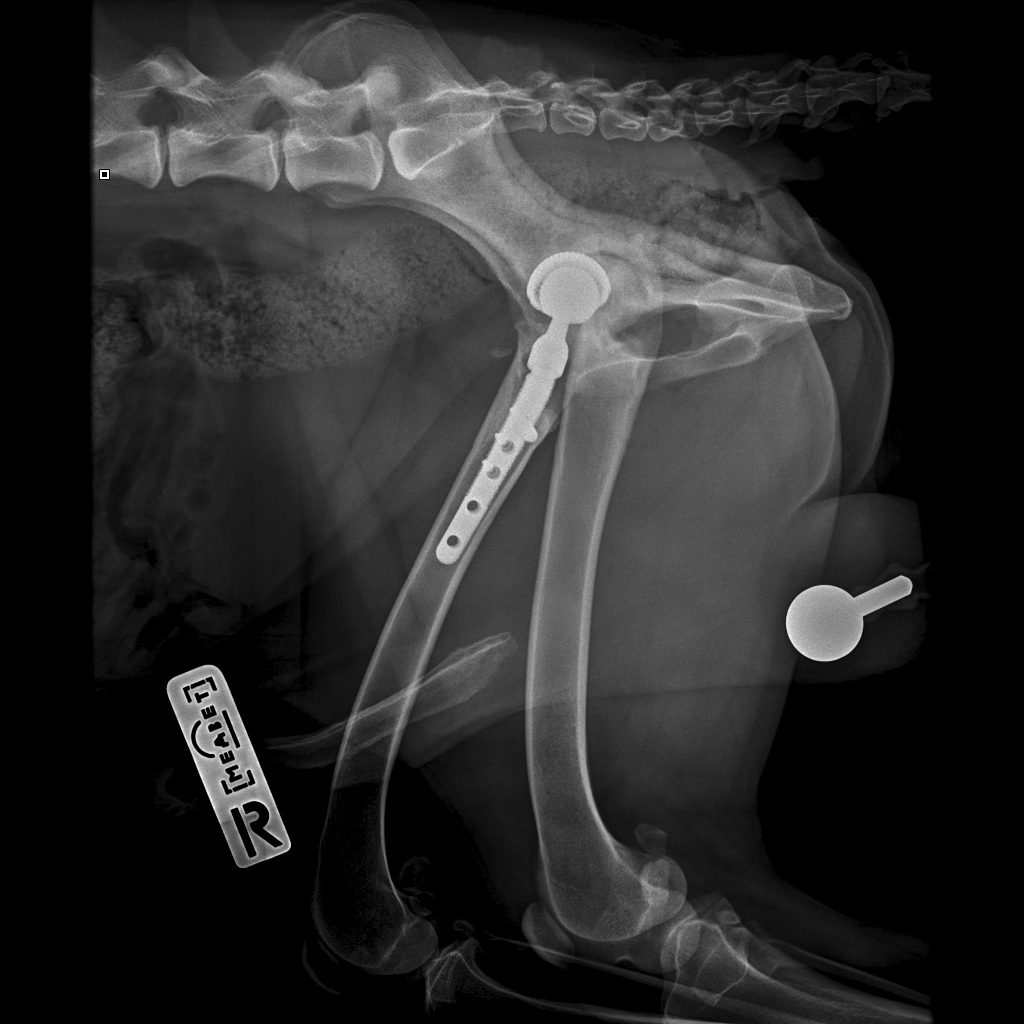

F37B4905-A77F-43B7-A3A7-4AAD9E739F82.jpeg

E6A744CC-768F-480D-8917-7FDAD53F05BD.jpeg

DA1A1524-BA63-434B-95BE-C121F7D5334F.jpeg

4D4A6426-4FE5-4417-ACCB-6DE53B57B90E.jpeg

E358D56E-67BF-4D4C-B3F0-BF8F4089D7A2.jpeg

767DD36C-E2E2-41FB-9CCF-6940421D2BB2.jpeg

701487DA-D6D9-4CE0-B18B-EEB120E78EF2.jpeg

Мы ничего не оплачивали. Все включено.

За время противовоспалительной терапии снизилось воспаление и в левом тазобедренном суставе, но увы, форма головки бедренной кости и состояние шейки бедра , лучше не стали:(((

Операция однозначно нужна.

Снимки столь качественные, что их можно в учебник